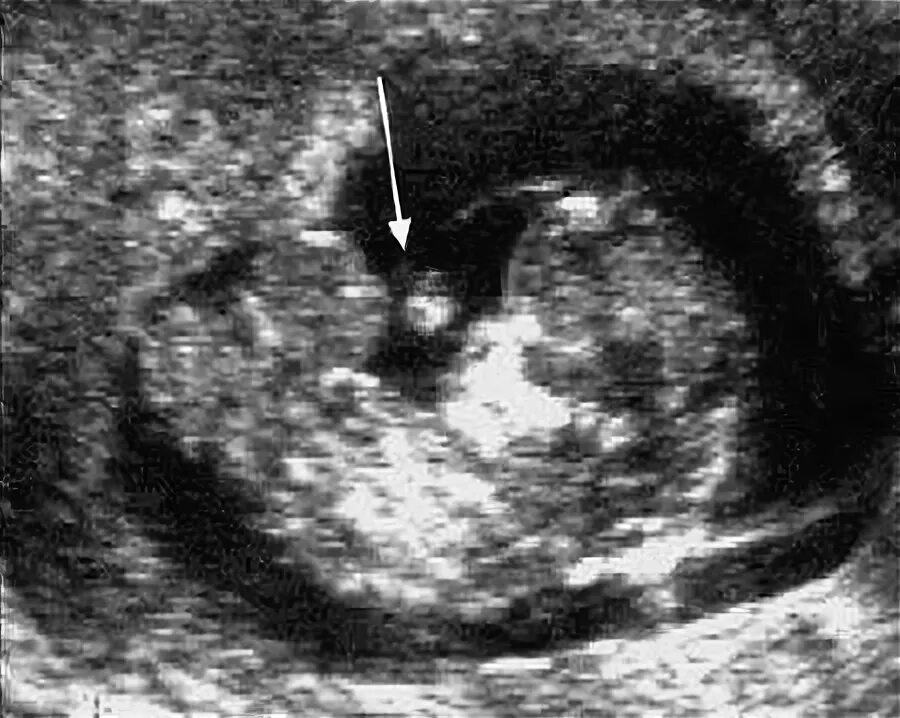

Желточный мешок увеличен